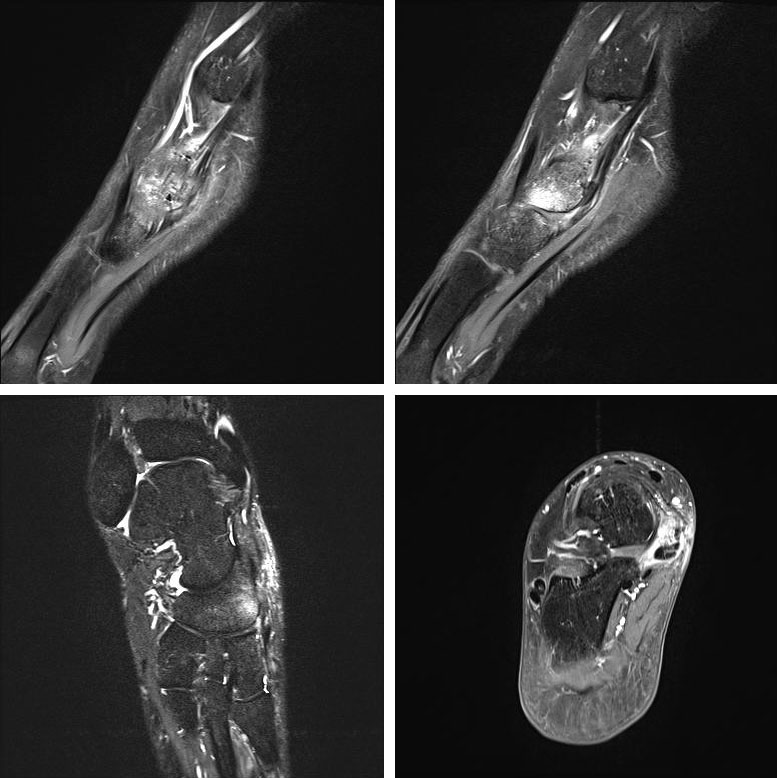

- Bei unklarem Befund kann die Bildgebung mittels MRTvervollständigt werden. Das MRT zeigt eine mögliche Aktivierung der Synchondrose bzw. erlaubt auch andere Differentialdiagnosen (Tendonose der Tibialis posterior Sehne, Verletzung Deltaband, Verletzung Pfannenband) auszuschließen (Abb. 3) 6 (Szeimies 2014).